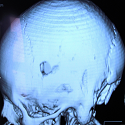

Depressed skull fracture secondary to the Mayfield three-pin skull clamp

Salami Mohcine, El Mostarchid Brahim

PAMJ. 2015; 20: 262. Published 19 March 2015